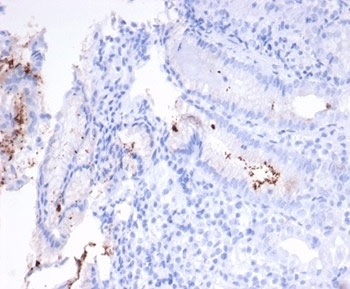

IHC staining of H. pylori-infected FFPE human stomach tissue with Helicobacter pylori antibody (clone HPYL/7227). HIER: boil tissue sections in pH 9 10mM Tris with 1mM EDTA for 20 min and allow to cool before testing.

IHC staining of FFPE H. pylori-infected human stomach tissue with Helicobacter pylori antibody (clone HPYL/7227). HIER: boil tissue sections in pH 9 10mM Tris with 1mM EDTA for 20 min and allow to cool before testing.

The spiral shaped bacterium Helicobacter pylori is strongly associated with inflammation of the stomach and is also implicated in the development of gastric malignancy. H. pylori is known to cause peptic ulcers and chronic gastritis in human. It is associated with duodenal ulcers and may be involved in development of adenocarcinoma and low-grade lymphoma of mucosa associated lymphoid tissue in the stomach. This antibody stains the individual H. pylori bacterium when it presents on the surface of the epithelium or in the cytoplasm of the epithelial cells in biopsy tissue sections from the antrum and body of the stomach.